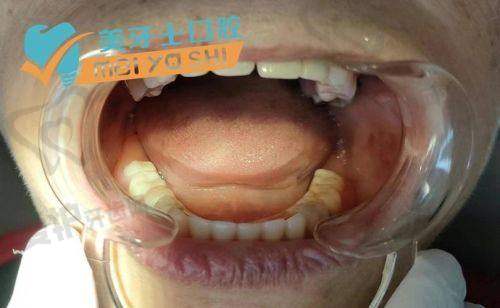

牙冠修复:当种植体与牙槽骨完全结合后,医生会为患者制作并安装牙冠。牙冠的制作需要根据患者的口腔情况和美观需求进行个性化设计,以确保牙冠的舒适度和美观度。安装牙冠后,患者就可以正常使用牙齿进行咀嚼和发音了。

在西安双宝口腔,有许多患者通过于洪海医生的半口牙种植手术,重新拥有了健康的牙齿。比如李先生,他因半口牙缺失多年,吃饭只能囫囵吞咽,身体也越来越差。在了解到西安双宝口腔的半口牙种植项目后,他抱着试试看的心态前来就诊。于洪海医生为他制定了详细的种植方案,并顺利完成了种植手术。术后,李先生修复良好,能够正常咀嚼食物,身体状况也逐渐改善。他对西安双宝口腔的技术和服务非常满意,称赞于洪海医生是一位医术不错、医德高尚的好医生。还有张女士,她因为半口牙缺失,面部凹陷,显得十分苍老。在于洪海医生的帮助下,她进行了半口牙种植。种植后,不仅牙齿修复了正常功能,面部美观也得到了极大提升,张女士重新找回了自信。